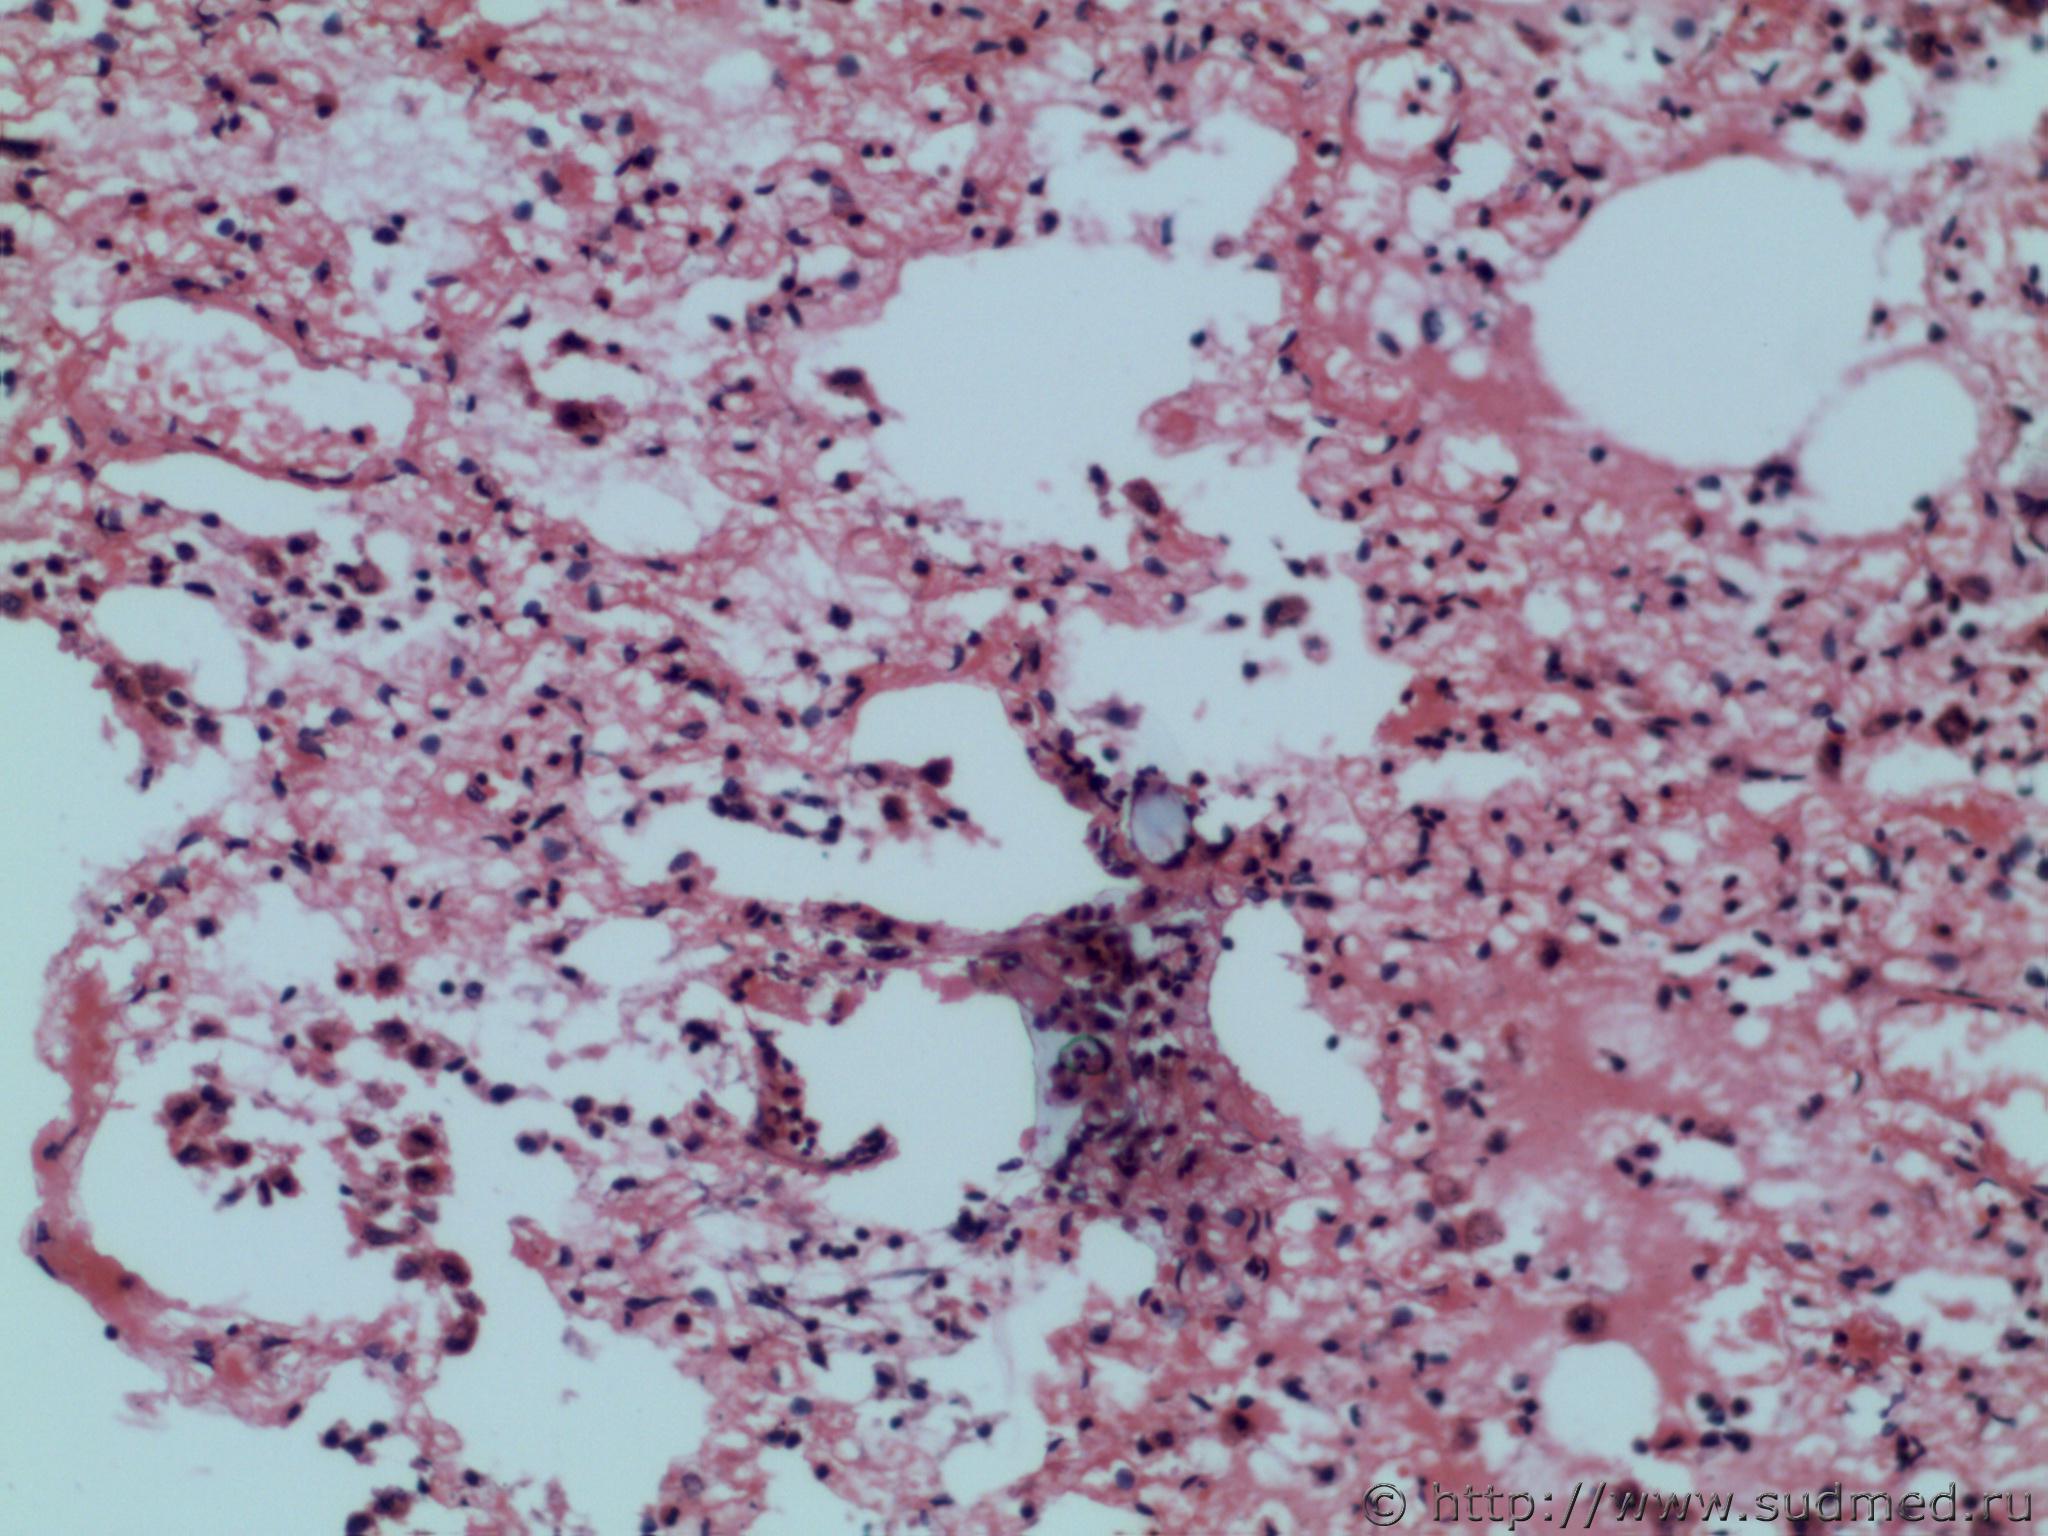

Аспирация желудочным содержимым (рвотными массами) и острая эмфизема, венозное полнокровие легких